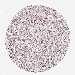

UROTHELIAL CANCER - Protein expressioni

A mouse-over function shows sample information and annotation data. Click on an image to view it in a full screen mode. Samples can be filtered based on level of antibody staining by selecting one or several of the following categories: high, medium, low and not detected. The assay and annotation is described here.

Note that samples used for immunohistochemistry by the Human Protein Atlas do not correspond to samples in the TCGA dataset.

Antibody stainingi

Antibody staining in the annotated cell types in the current human tissue is reported as not detected, low, medium, or high, based on conventional immunohistochemistry profiling in selected tissues. This score is based on the combination of the staining intensity and fraction of stained cells.

Each image is clickable and will lead to virtual microscopy that enables deeper exploration of all samples and also displays staining intensity scores, fraction scores and subcellular localization as well as patient and tissue information for each sample.

Antibody HPA045663

Antibody HPA051631

Staining

High

Medium

Low

Not detected

Intensity

Strong

Moderate

Weak

Negative

Quantity

>75%

75%-25%

<25%

None

Location

Nuclear

Cytoplasmic/membranous

Cytoplasmic/membranous,nuclear

Urothelial carcinoma, High grade